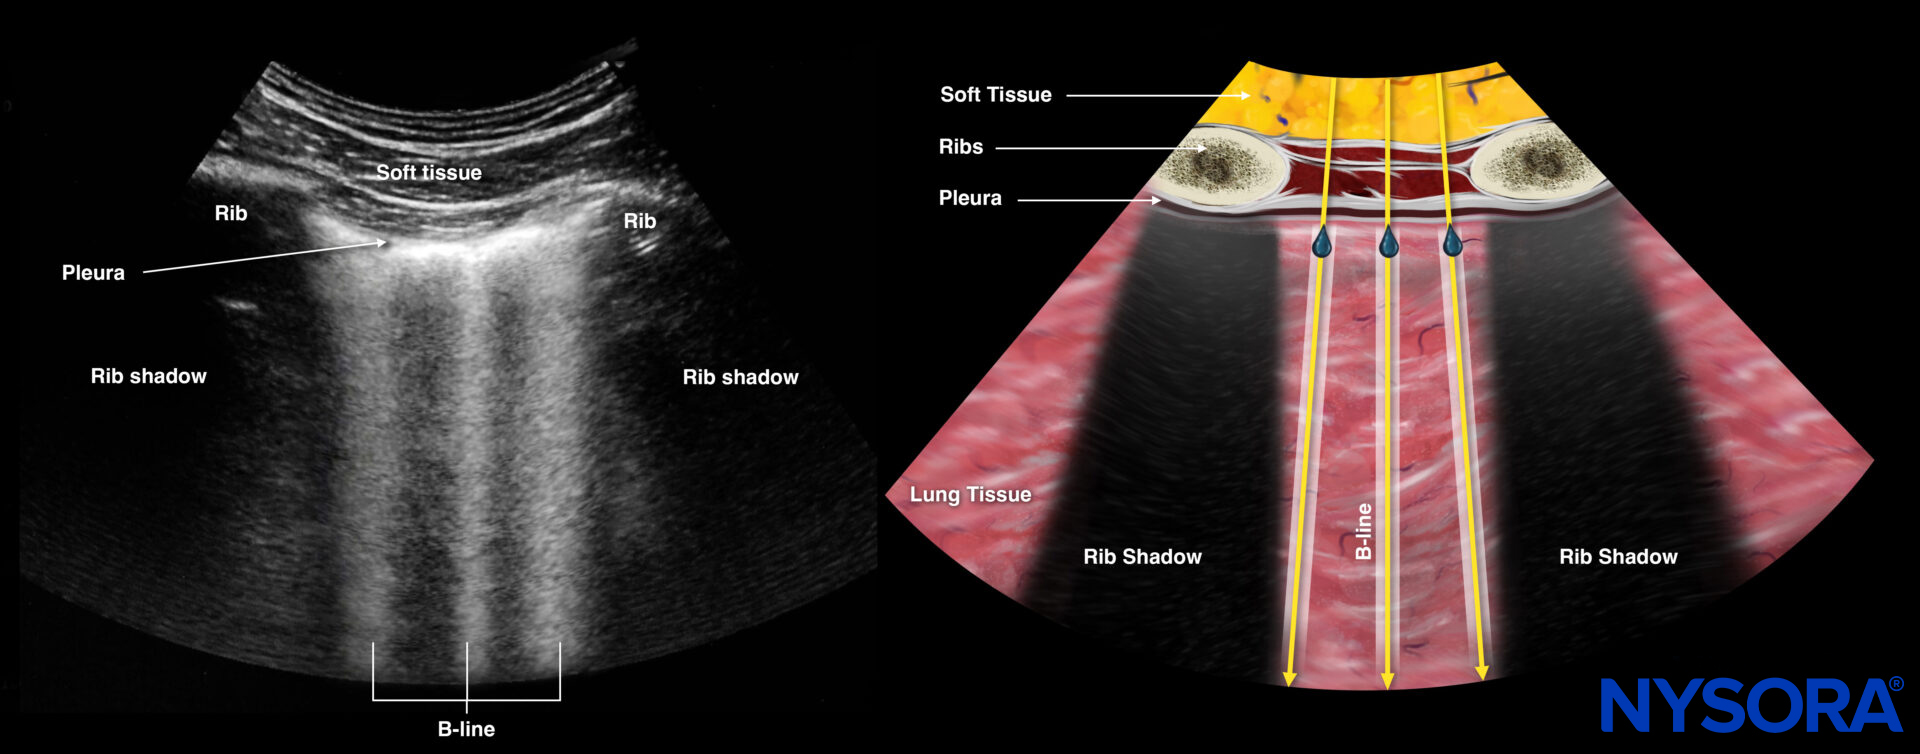

Next, scan the 4 BLUE points. B-lines represent extravascular lung water, and 3 or more B-lines in all 4 BLUE points (B-profile) are likely to be pulmonary edema.

Sonography and Reverse Ultrasound Anatomy of B-lines.